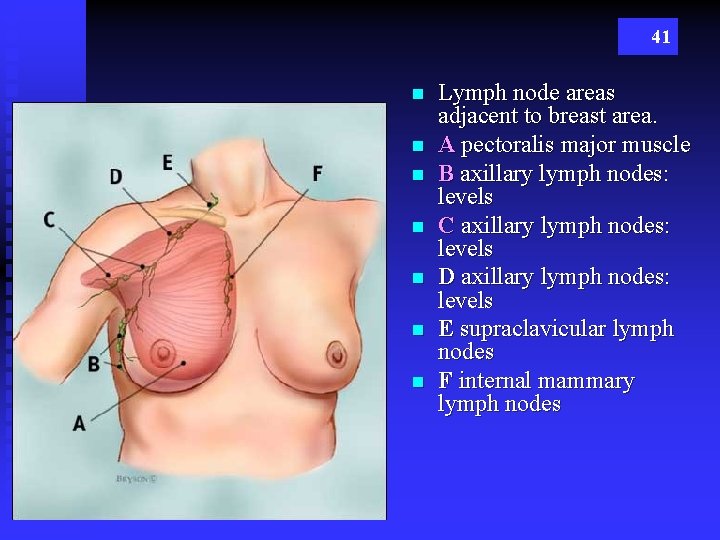

41 n n n n Lymph node areas adjacent to breast area. A pectoralis major muscle B axillary lymph nodes: levels C axillary lymph nodes: levels D axillary lymph nodes: levels E supraclavicular lymph nodes F internal mammary lymph nodes

Lymph Nodes n Lymphatic vessels of the breast drain laterally and medially u Laterally into the axillary lymph nodes (C & D) t 75& drain toward axilla u Medially into the mammary lymph nodes t 25% toward mammary chain (F) 42